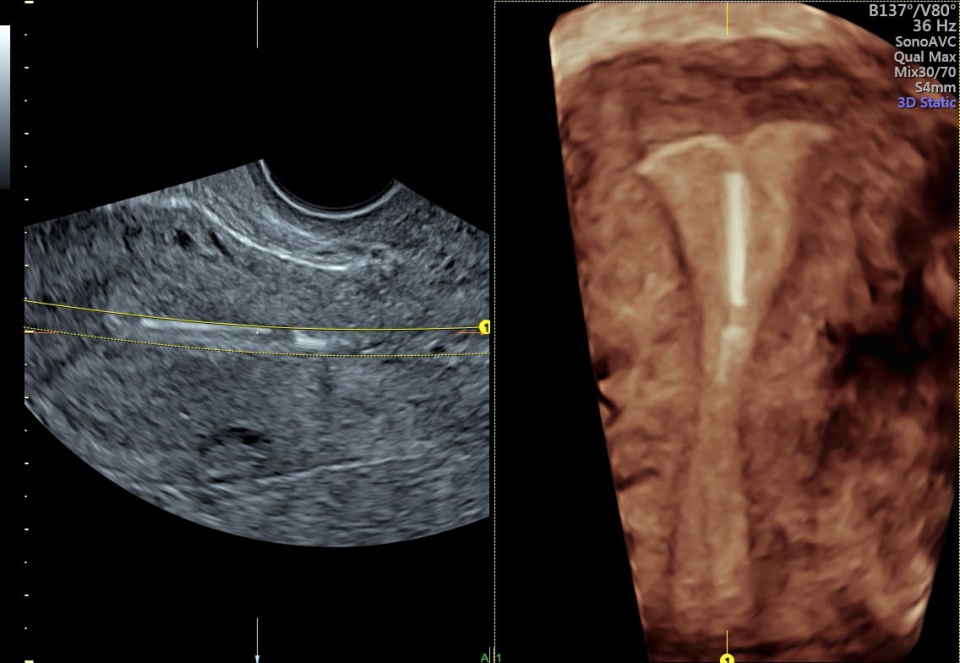

УЗИ аппарат Voluson S10 позволяет проводить обследования высочайшего уровня с максимальной точностью диагностики. Благодаря технологии Voluson Core Architecture достигнут высокий уровень качества изображений с возможностью последующей обработки и анализа даже после проведения скрининга. Технология HDlive делает изображения удивительно реалистичными и объемными.

• SonoRenderlive (Автоматическое объемное изображение): Эта функция упрощает получение объемного изображения путем автоматического выбора положения плоскости визуализации для 3D- и 4D-режимов. Это сокращает необходимость вручную настраивать параметры и упрощает процесс получения объемных изображений.

• SonoAVC (Автоматический расчет объема): Эта функция позволяет визуализировать и рассчитывать размеры и объем гипоэхогенных образований, таких как фолликулы яичника или структуры головного мозга плода. Она помогает в оценке этих образований и отслеживании их изменений в течение времени.